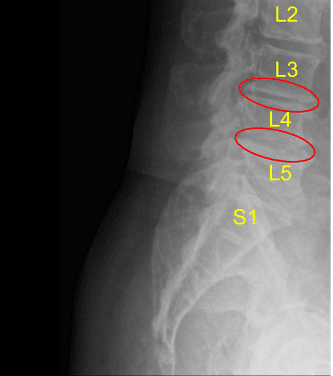

Postoperative X-ray

AP and lateral radiographs indicated excellent cage positioning, restoration of lordosis, and indirect decompression throughout. Accordingly, the L3-L4 cage was released from the cage inserter. The area was copiously irrigated with antibiotic impregnated saline and packed with Surgiflo hemostatic matrix product.

Accordingly, the case was felt completed with a two-level anterolateral interbody fusion being performed very efficiently at the L3-L4 and L4-L5 levels. The abdominal fascia was reapproximated with interrupted figure-of-eight #0 Vicryl sutures followed

The patient followed up in two weeks after the surgery and showed signs of improvement. The patient also then continued to follow up in 4, 6, 8, 12, 24 weeks. In their last office visit the patient stated they were able to do their usual activities.

Postoperative X-ray Saggital View

Postoperative X-ray Sagittal View